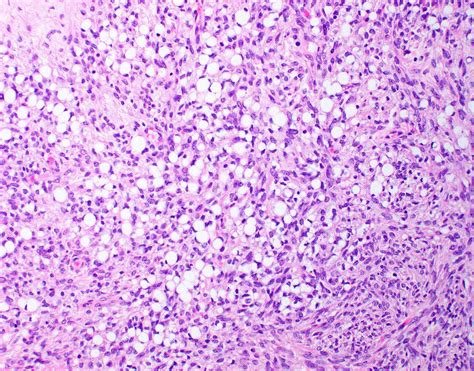

In the field of pathology and oncology, identifying specific cellular abnormalities is crucial for accurate diagnosis and determining the best course of treatment. Among these, Signet Ring Cells stand out due to their distinct appearance under a microscope. These cells are characterized by a large, central vacuole filled with mucin, which pushes the nucleus to the periphery, giving the cell a shape reminiscent of a traditional signet ring. Understanding what these cells represent, how they form, and the conditions associated with them is vital for both medical professionals and patients seeking clarity on diagnostic reports.

Signet Ring Cells are a specific type of abnormal cell often associated with certain forms of cancer, most notably adenocarcinoma. The "signet ring" appearance is not a type of cell in itself, but rather a morphological feature that a cell takes on due to the intracellular accumulation of mucin—a substance similar to mucus. As the mucin accumulates, it expands the cell's cytoplasm, effectively displacing the nucleus to the edge of the cell membrane. This structural change is a hallmark that pathologists look for when examining biopsy samples, as it often indicates a higher potential for malignancy and aggressiveness.

The discovery of Signet Ring Cells typically occurs during a biopsy, where a tissue sample is removed and processed for histological examination. Pathologists use specialized staining techniques to confirm the presence and nature of these cells. For instance, stains like periodic acid-Schiff (PAS) are used to highlight the mucin within the cell, confirming its chemical composition. Understanding the density and distribution of these cells is essential for staging the cancer, which directly influences the treatment plan.

Microscopic Appearance Large mucin vacuole, eccentric nucleus